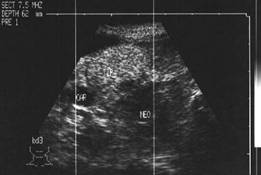

Tiroida normala

Ecostrutura omogena, normoecogena. Dimensiuni normale.

Se urmaresc rapoartele cu carotida, jugulara, muschii, traheea, esofagul.